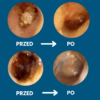

Koniec z ryzykiem urazów i infekcji — patyczki często powodują podrażnienia, infekcje i perforację błony bębenkowej. Pełna kontrola dzięki obrazowi HD 1080p — widzisz woskowinę i swobodnie ją usuwasz, zamiast ją wpychać.

Pełna kontrola dzięki obrazowi HD 1080p — widzisz woskowinę i swobodnie ją usuwasz, zamiast ją wpychać. Miękkie silikonowe końcówki zamiast patyczków — precyzyjnie usuwa woskowinę, bez ryzyka zarysowań i dyskomfortu